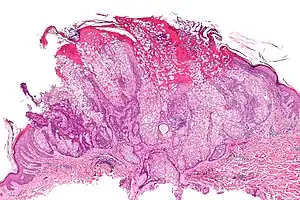

| Micrograph of a sebaceous adenoma, as may be seen in Muir–Torre syndrome. H&E stain. | |